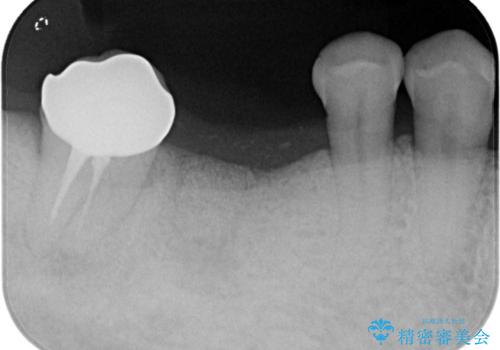

- 奥歯の欠損をインプラントで治療したいと来院された患者様です。

骨の状態が安定するまで待機したのち、インプラントを埋入しています。